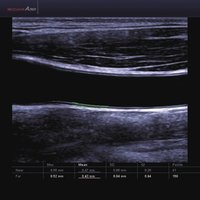

• ElastoScan™ ermöglicht eine genauere Visualisierung von Tumoren und erfasst und dokumentiert Gewebesteifheiten.

• Das Tissue Specific Imaging (TSI) optimiert die Qualität des Scans anhand der Beschaffenheit des Gewebes. Es kann aus 4 unterschiedlichen Bildmodi gewählt werden: Allgemein, Muskel, Fließend, Fett.

1 L4-7 Linear 4-7 MSK, Gefäße, Tiefe Venen

2 L5-13IS Linear 6-12 MSK, Weichteile, Gefäße, Brust

3 L5-13/50mm Linear 5-13 MSK, Weichteile, Gefäße

4 LS6-15 Linear 6-15 MSK, Weichteile, Gefäße

5 L7-16IS Linear 7-16 MSK, Weichteile, Gefäße, weibliche Brust, Pädiatrie, Oberfläche